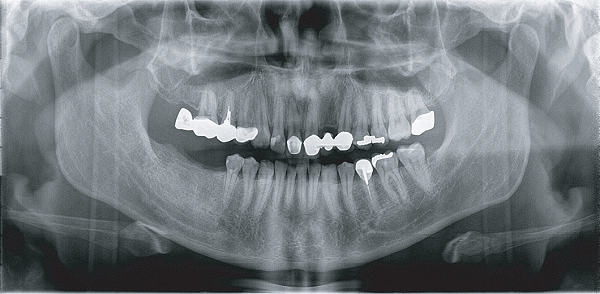

Apsaras 3D 口腔頜面錐形束計算機體層攝影設(shè)備

臨 床 圖 集